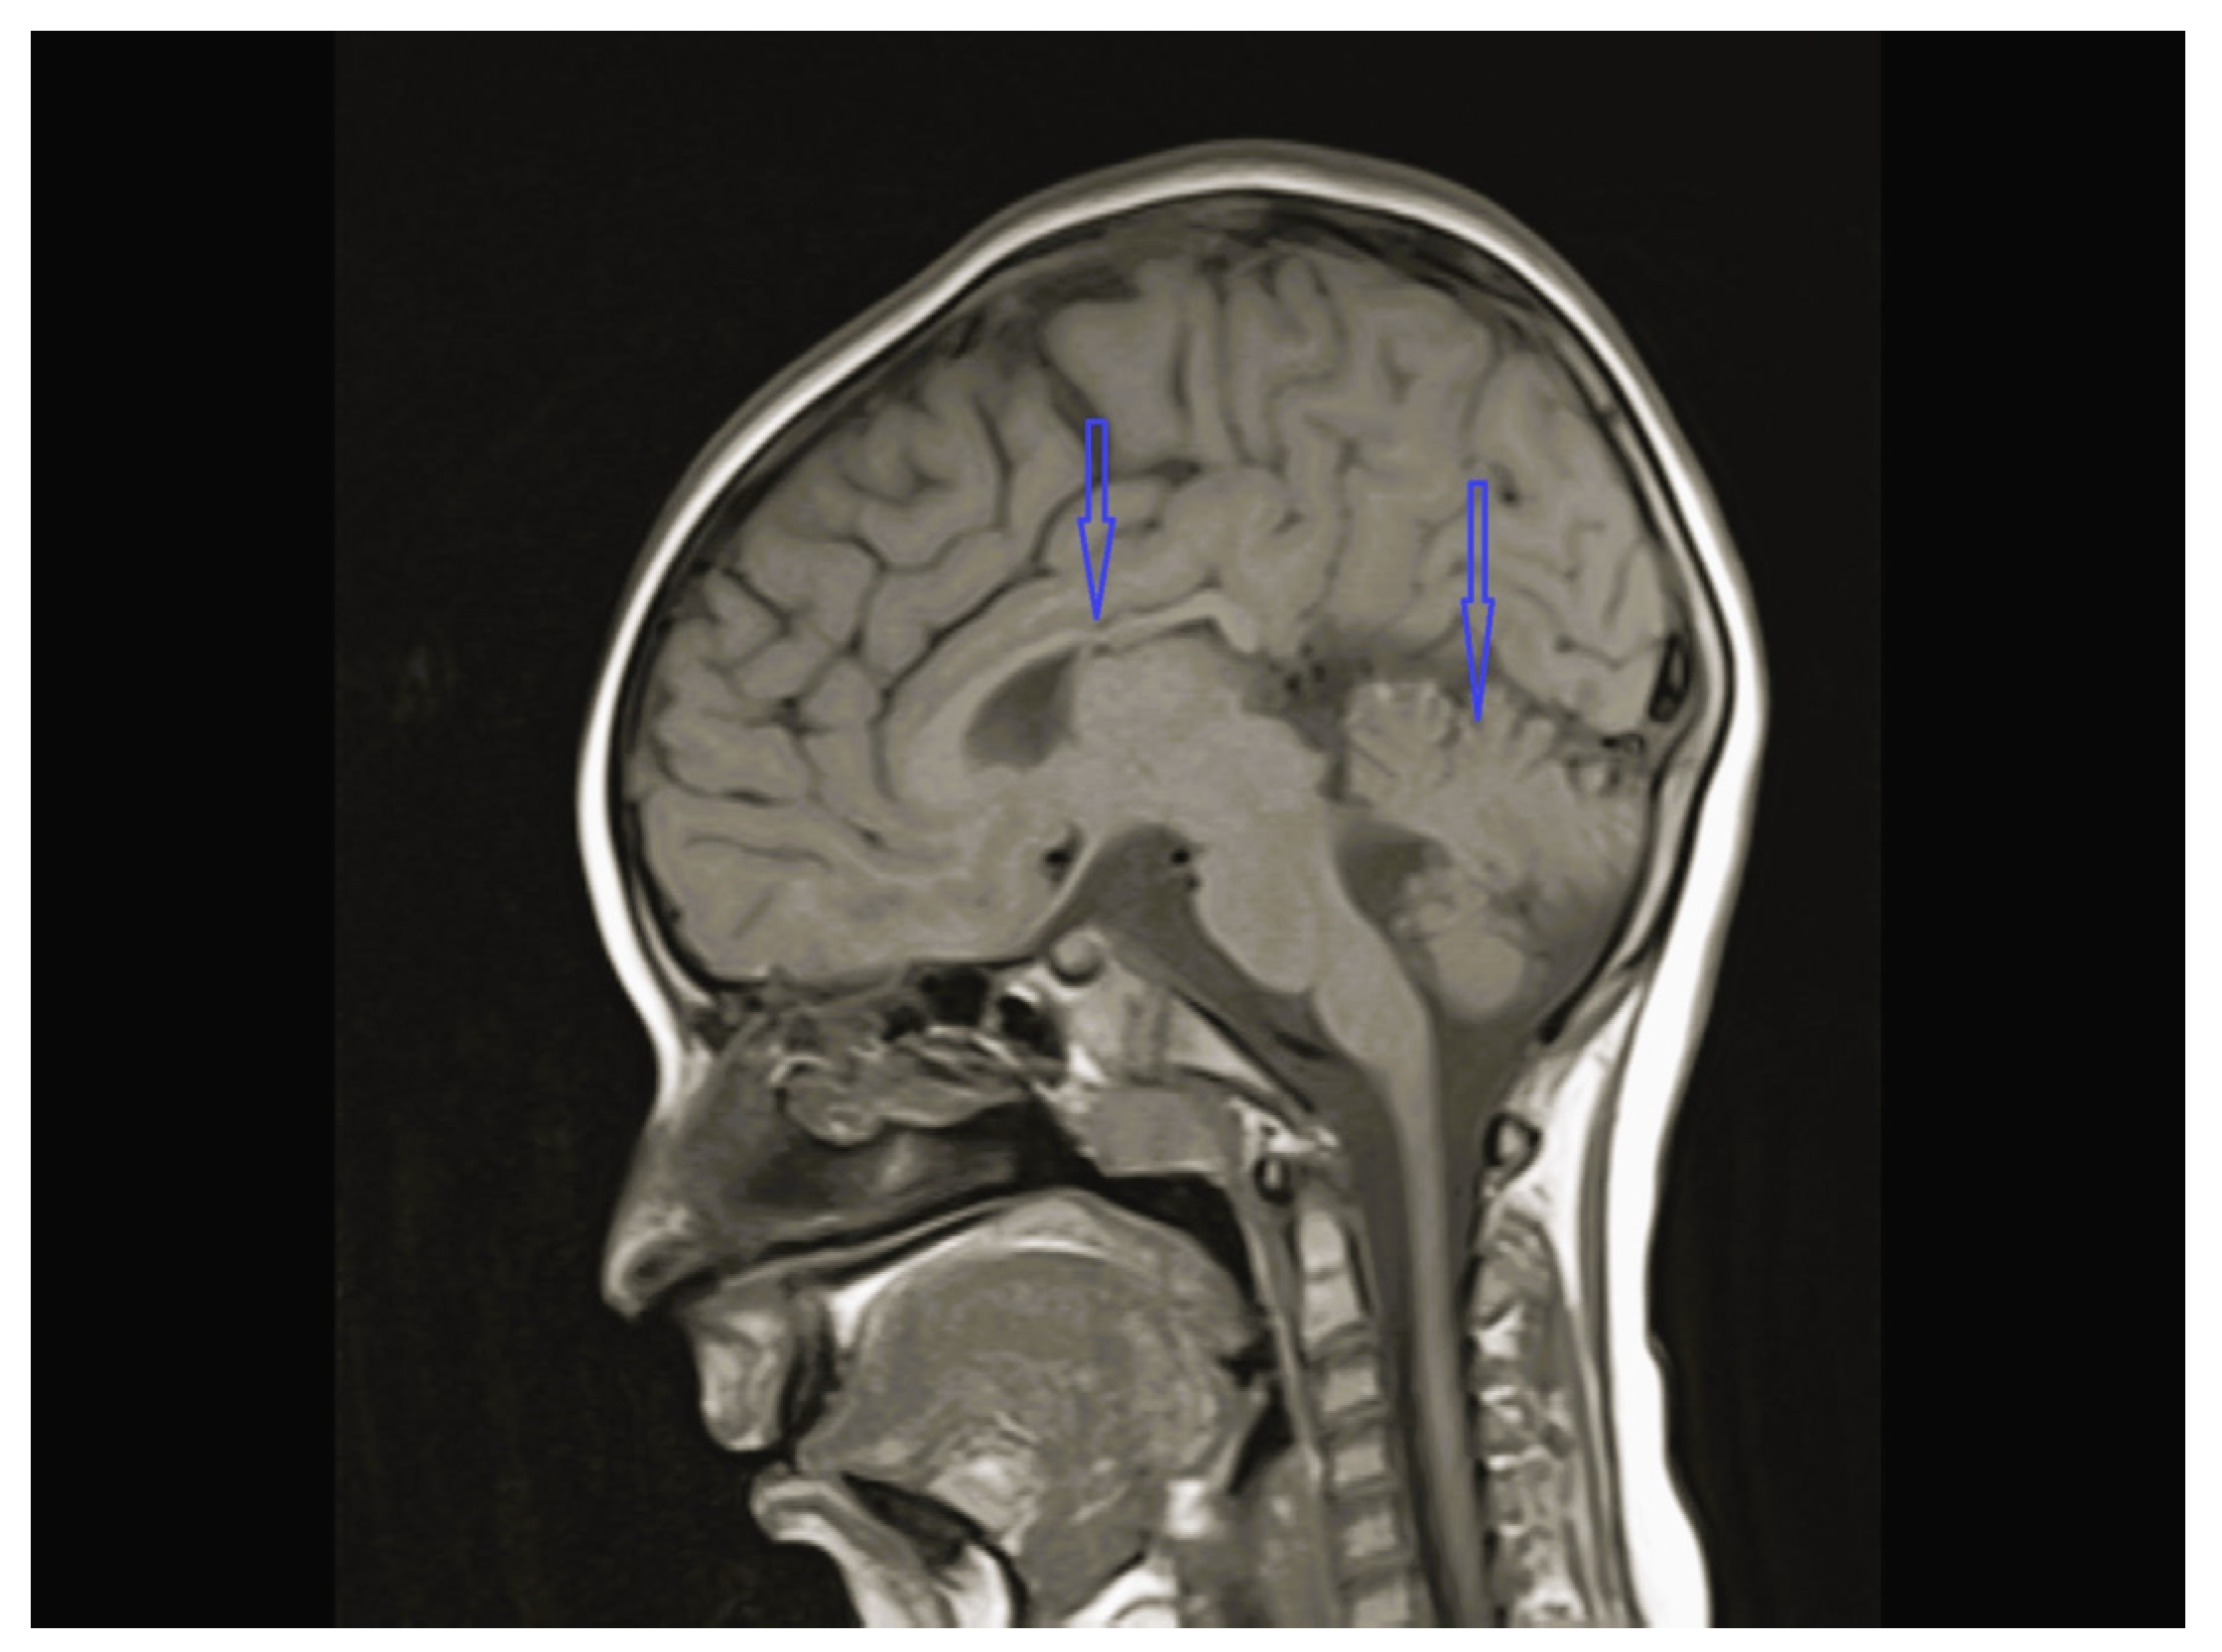

| 1 | - | - | - | Cerebellar hypoplasia, vermis dysplasia and corpus callosum (CC) hypoplasia | Normal | SPG11 c.6730C>T heterozygote (p.L2244F) | Physical therapy |

| 3 | Normal | - | Normal | Vermis and CC hypoplasia | Normal | KIF1A c.773C>T heterozygote (p.V391M) | Physical therapy, baclofen |

| 8 | Normal | - | Multifocal spike and waves pattern | Vermian, CC and brainstem hypoplasia | Normal | KIDINS220 NM_020738.4 c.4388C>A heterozygote p.S1463* | Physical therapy, clonazepam, sodium valproate |